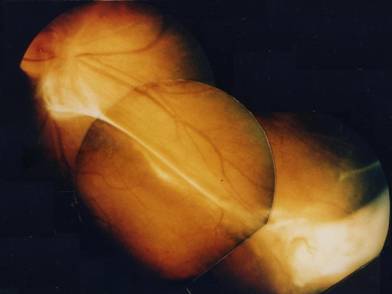

The major causes of visual acuity loss are: - severe vitreitis (52.6% of the cases), - cystoid macular edema (47,4%) and - tractional retinal detachment (36.8%) (Figure 1). [2] The real factors that may influence the onset of a determined clinical form are unknown. It is possible that the lesions are due to a toxic or immunoallergic reaction towards larval antigens, mainly associated with larval death. The disruption occurring after larval death may determine an inflammatory reaction and granuloma formation. The associated vitreitis is usually considered a reaction towards highly immunogenetic antigens. The severity of the disease might be related to the number of the larvae present in the eye and by the immune response of the host.

Figure 1

Ocular toxocariasis with peripheral granuloma and vitreoretinal traction.